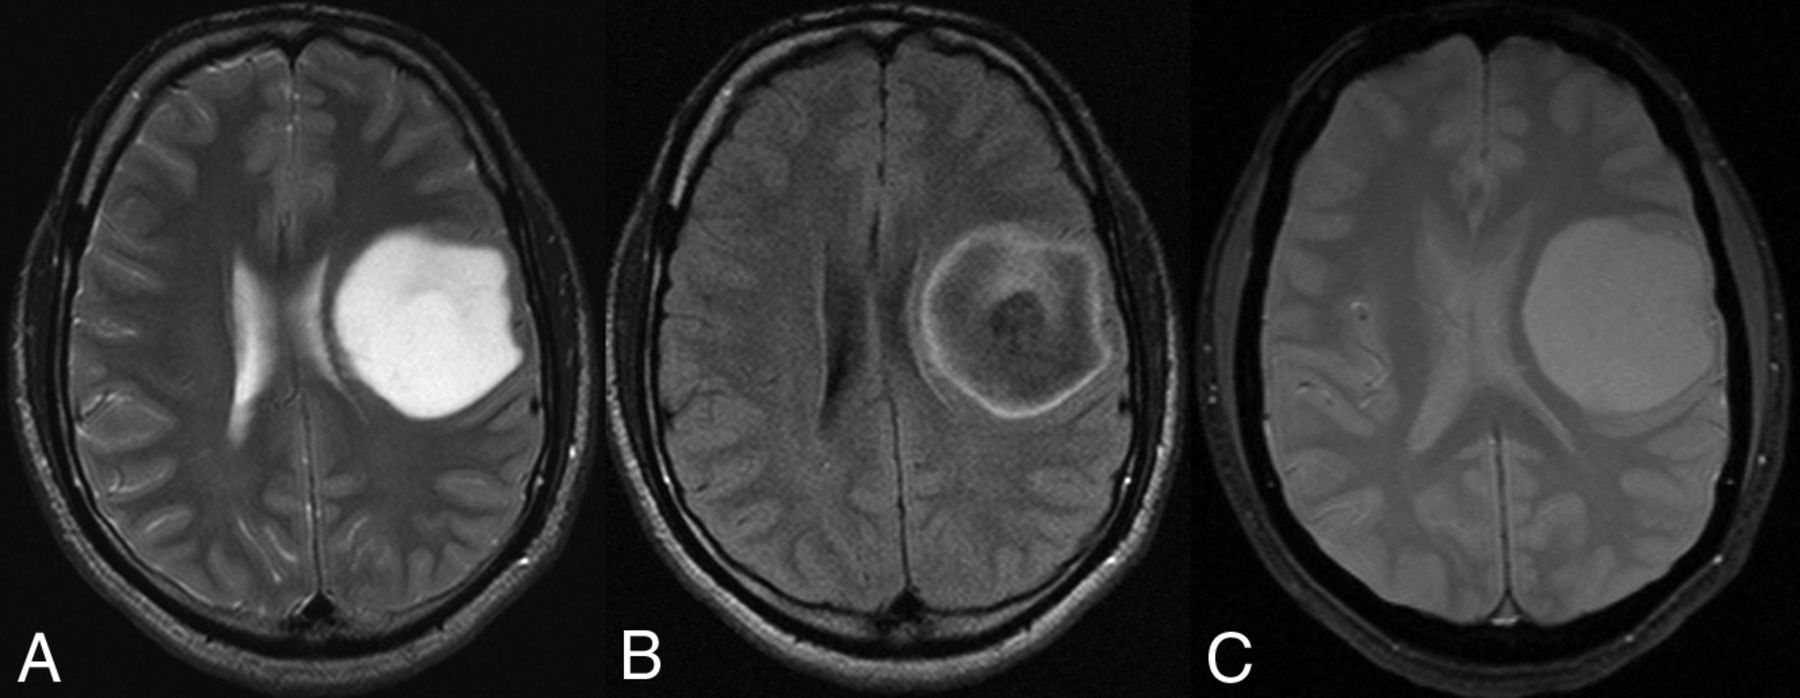

A 54-year-old woman with a left frontal lobe oligodendroglioma, IDH-mutant and 1p/19q-codeleted, showing characteristic imaging features. A and B, T2WI and FLAIR demonstrate a heterogeneous and poorly marginated mass with significant cortical infiltration and no T2-FLAIR mismatch sign. C, T2*WI shows regions of striking susceptibility blooming.

Two neuroradiologists, with 5 and 13 years of experience, blinded to the 1p/19q-codeletion status, analyzed the MR images from the training dataset in consensus. They measured 14 neuroimaging metrics: 1) primary lobe: yes/no centered on frontal lobe; 2) texture: more or less than 75% of the tumor showing homogeneous signal intensity on T1WI/T2WI; 3) margins: more or less than 75% of the tumor showing sharp/circumscribed margins; 4) T2-FLAIR mismatch sign: the presence or absence of complete/near-complete hyperintense signal on T2WI and relatively hypointense signal on FLAIR except for a hyperintense peripheral rim19; 5) T2* susceptibility blooming: present or absent; 6) contrast enhancement: present or absent; 7) cysts: present or absent; 8) necrosis: present or absent; 9) maximum tumor diameter (centimeter); 10) cortical infiltration: present or absent; 11) peritumoral edema: present or absent; 12) gliomatosis: yes/no involvement of ≥3 lobes; 13) midline shift (centimeter); and 14) hydrocephalus: present or absent. Figures 1 and 2 show the characteristic imaging appearance of IDHmut-Noncodel and IDHmut-Codel LGGs, respectively, including a description of several of the above imaging metrics. Univariate and multivariate logistic regression analysis of the MR imaging characteristics and patient age for predicting the 1p/19q-codeletion status was undertaken. On the basis of these results, a classification algorithm for 1p/19q prediction was developed.